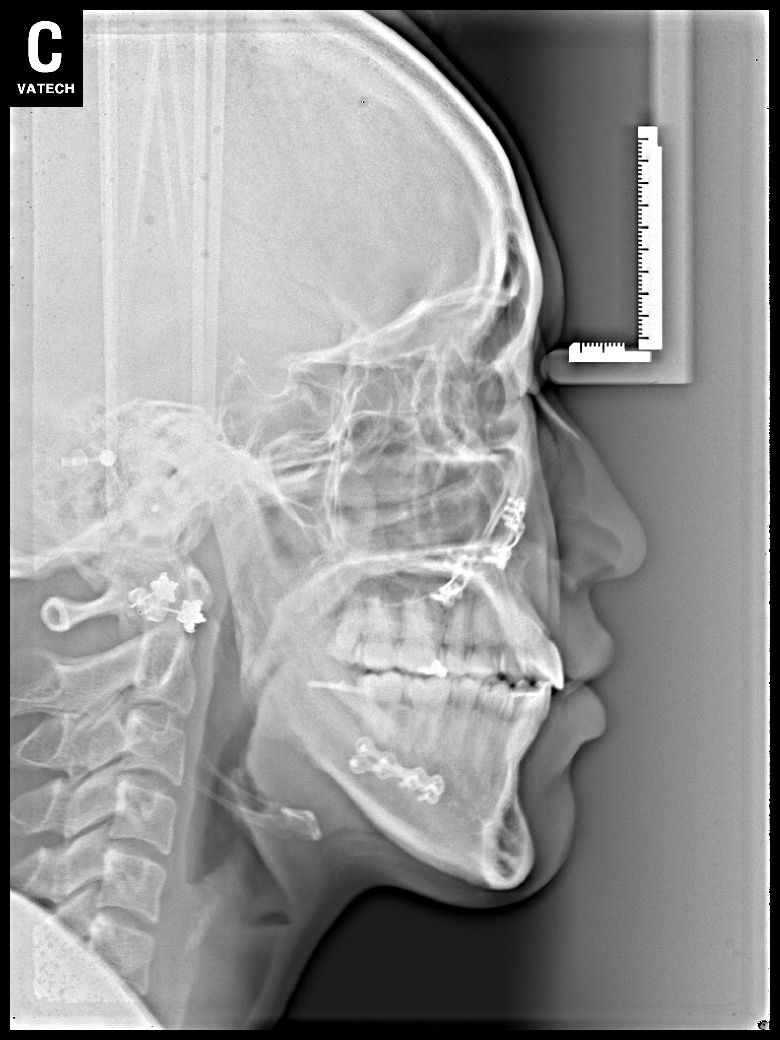

치료 후 사진입니다.